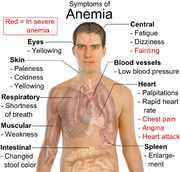

| 26. 5. 2010, 08:28 | Symptomy anemie.png (soubor) |  | 341 kB | Webmaster | 1 | |